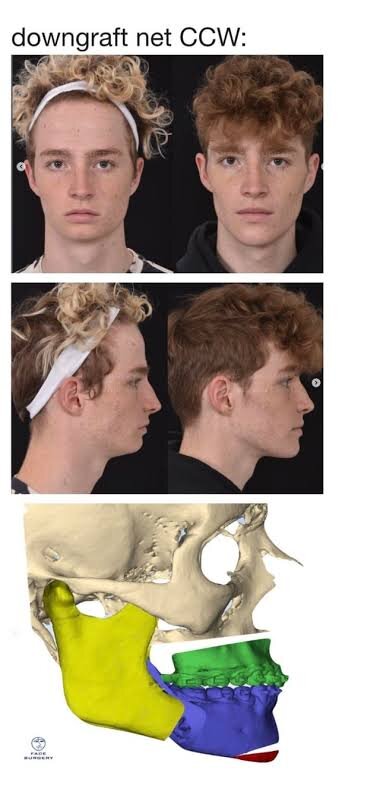

Rate my trimax

17 btw, cost 4.5K€

Before and after

I'm 4 weeks post surgery, so still pretty much swelling is left